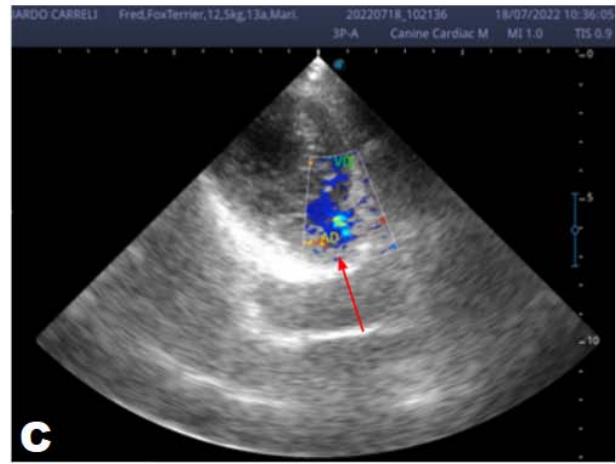

One year later, the animal returned for a new evaluation, repeating the ECHO (Figure 2), which showed the progression of the increase in the left atrium. The electrocardiogram (ECG) (Figure 3) shows baseline sinus arrhythmia with the presence of a premature ventricular complex (Figure 4). Owners report drowsiness, hyporexia, and syncope. However, they did not present tiredness or cough. Blood pressure was 80 mmHg.

Figure 2: Echocardiogram (2022): observed increase in the left atrium and ventricle; thickened/degenerated mitral valve (A); observed in a Doppler study, turbulent systolic flow within the left atrium, characterizing significant mitral valve insufficiency (B); systolic turbulent flow within the right atrium, representing mild tricuspid valve insufficiency (C); hemodynamic assessment - maximum velocity gradient mitral regurgitation: $3.51\mathrm{m / s} / 49.22\mathrm{mmHg}$; observed left ventricular diastolic dimension above normal limits with normal systolic function parameters, characterizing systolic dysfunction; preserved diastolic function

In 2022, the animal returned for annual exams one year after the diagnosis. The ECHO showed an increase in the left atrium and ventricle, thickened/degenerated mitral valve (Figure 2), preserved diastolic function, and low probability of pulmonary hypertension; the ECG detected an increase in the duration of the P wave and the QRS complex (Figure 3), suggestive of atrial and left ventricular overload, baseline sinus arrhythmia with the presence of a premature ventricular complex.